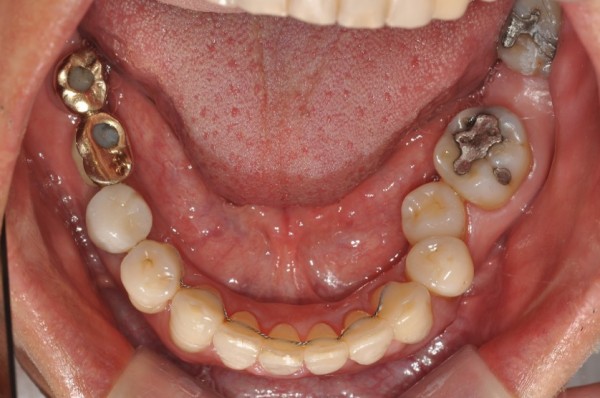

치료 전후사진

Before & After

앞니 부분교정 / 중장년 교정

서울린교정치과

*50대 남성 *아래 앞니만 부분교정 *치료기간: 6개월